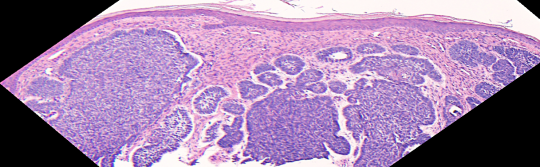

VA33: Superior Nasal Ala, Basal Cell Carcinoma, Nodular

- * indicate areas of necrotic cells not yet undergone liquifactive necrosis